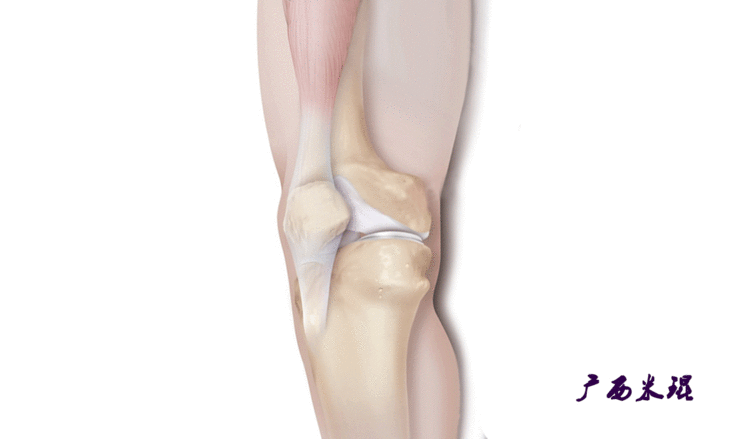

说到髌骨脱位,首先就要了解髌骨,髌骨是人体最大的籽骨,倒三角状位于膝关节前方,它的上缘与股四头肌腱相连,下缘通过髌韧带止于胫骨结节上,两侧为股四头肌扩张部,髌骨后方的凸面为光滑的关节面,与股骨下端内外髁之间的滑车凹面关节面形成关节。尽管股四头肌中的股直肌、股中间肌、股外侧肌的作用方向与髌韧带不在一条直线上,髌骨有向外突出的倾向,但因股内侧肌有向内上方牵拉作用力而使髌骨维持在正常位置。